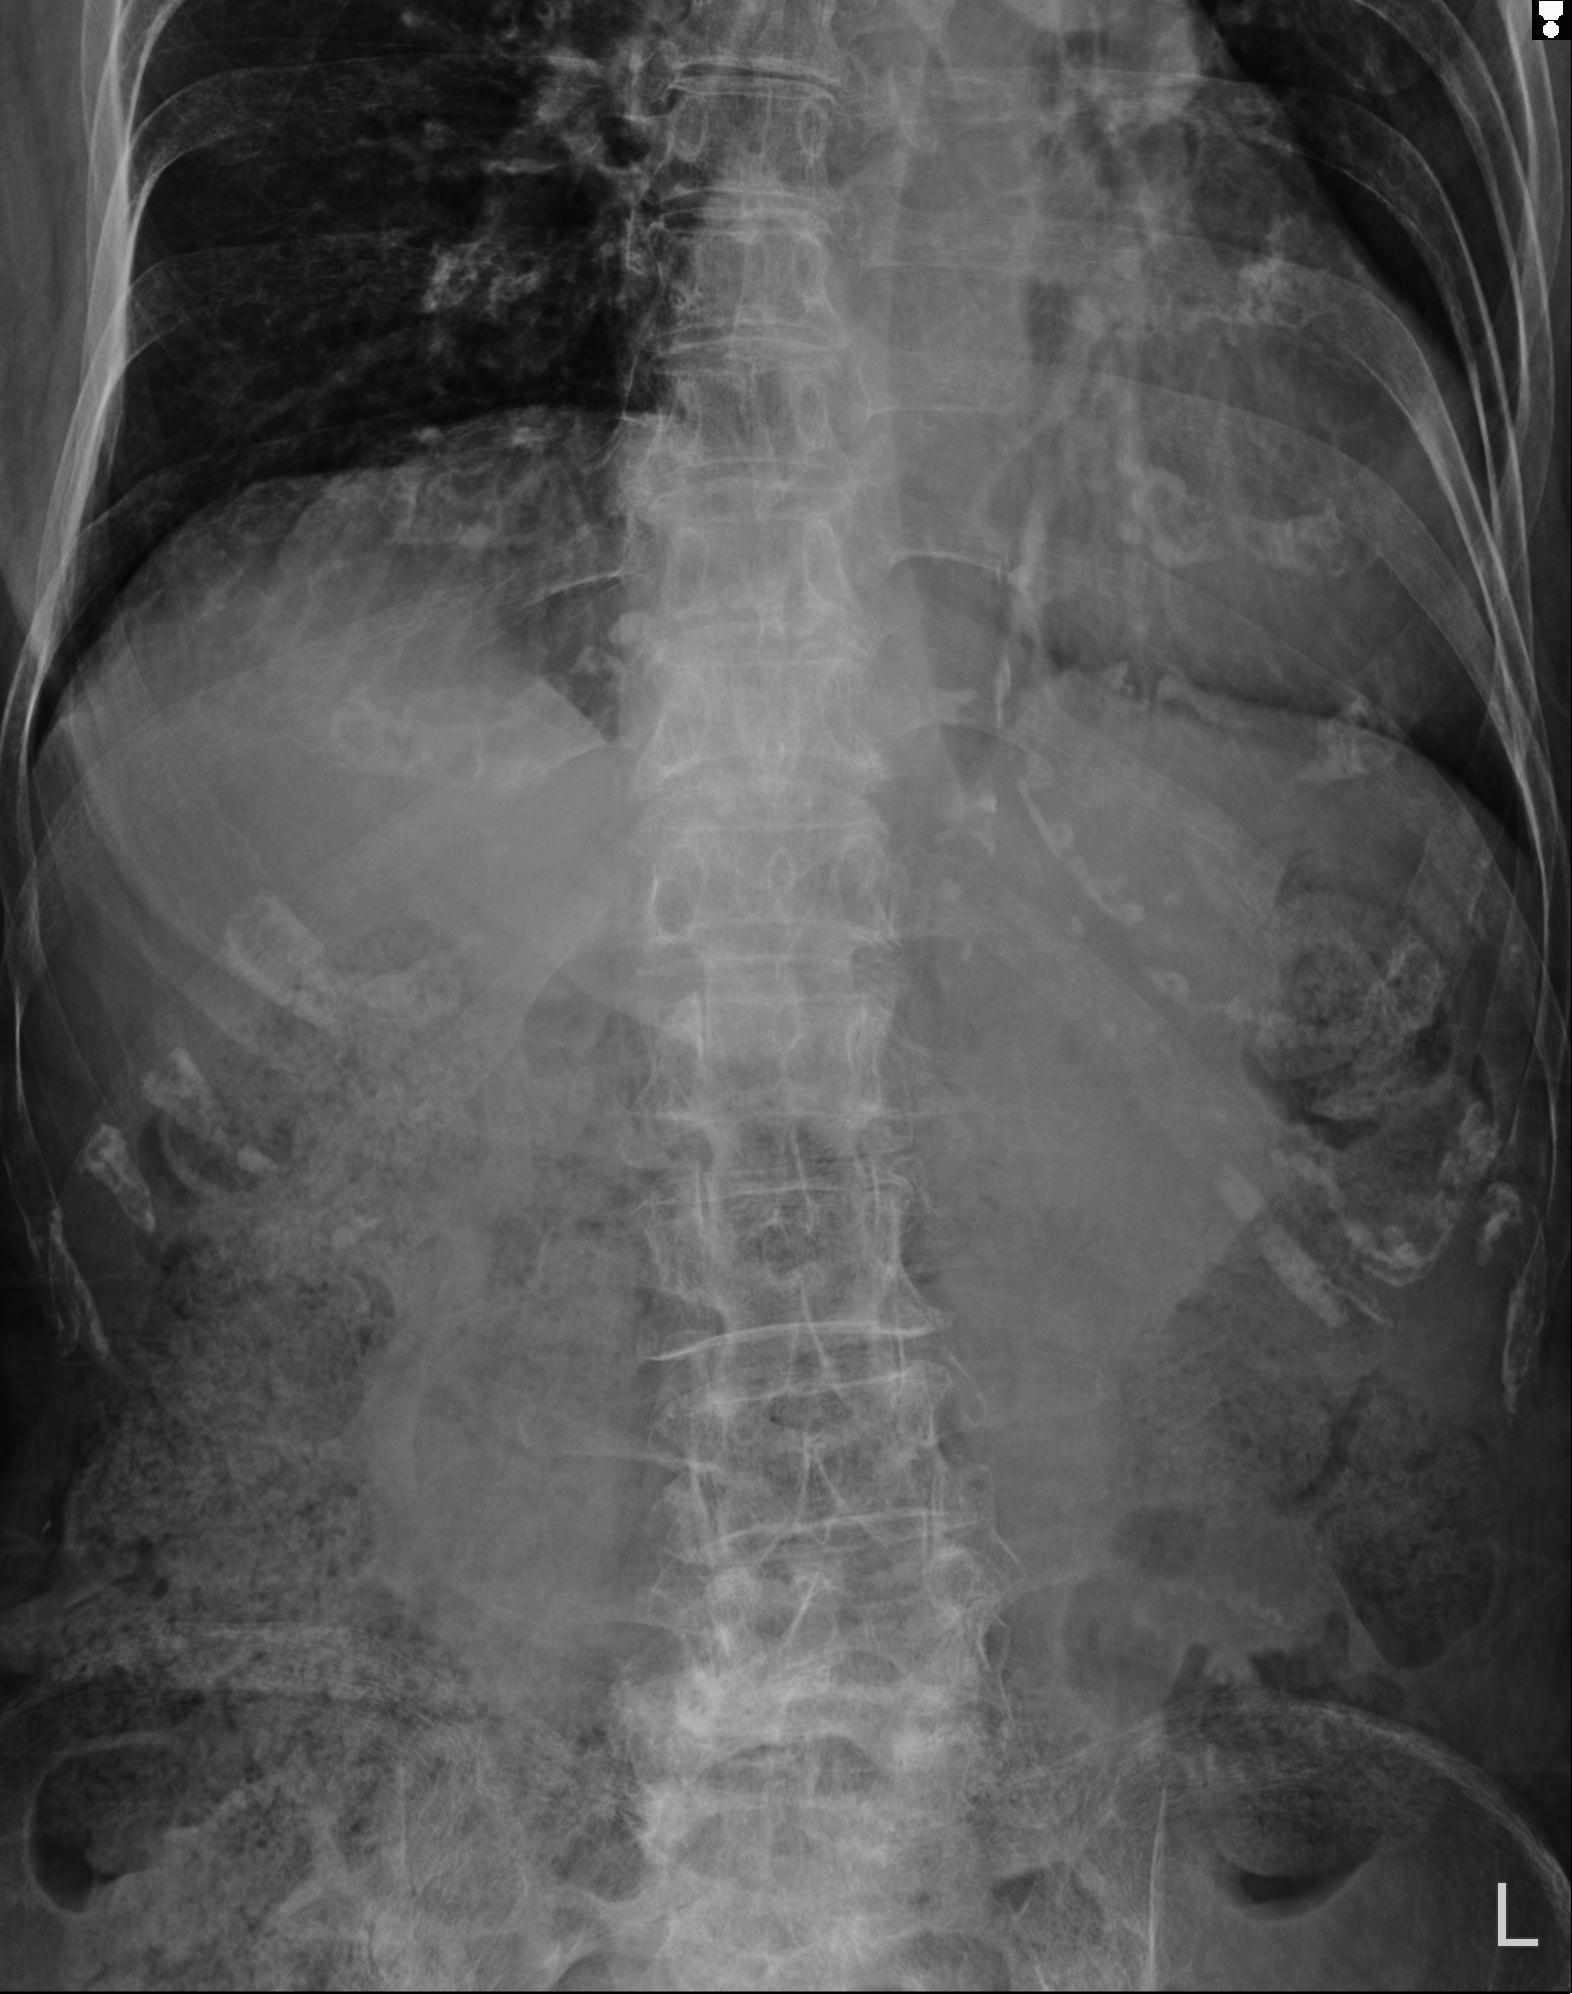

102755 1/4 2R 1/15 2R 右足関節 68歳女性 右三果脱臼骨折